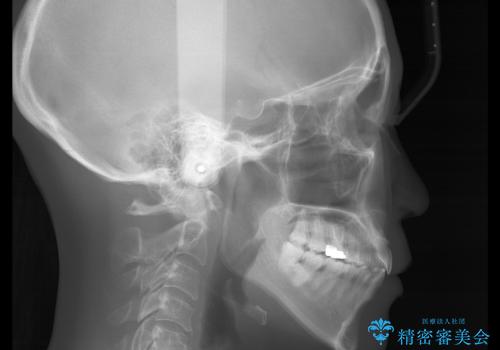

- 歯ぐきと骨が薄く、他院にて大きな矯正治療を断られた患者様です。

ワイヤー治療で行う場合、抜歯治療が第一選択となりますが、

骨と歯茎の状態を考慮した場合、抜歯をして大きく動かすことは避けたいと考えました。

そこで、インビザライン矯正で非抜歯で行うことを提案させて頂きました。

抜歯を行うことが困難であり、また歯ぐきと骨が薄いことで

拡大と呼ばれる歯のアーチを広げる処置を行うことも困難でした。